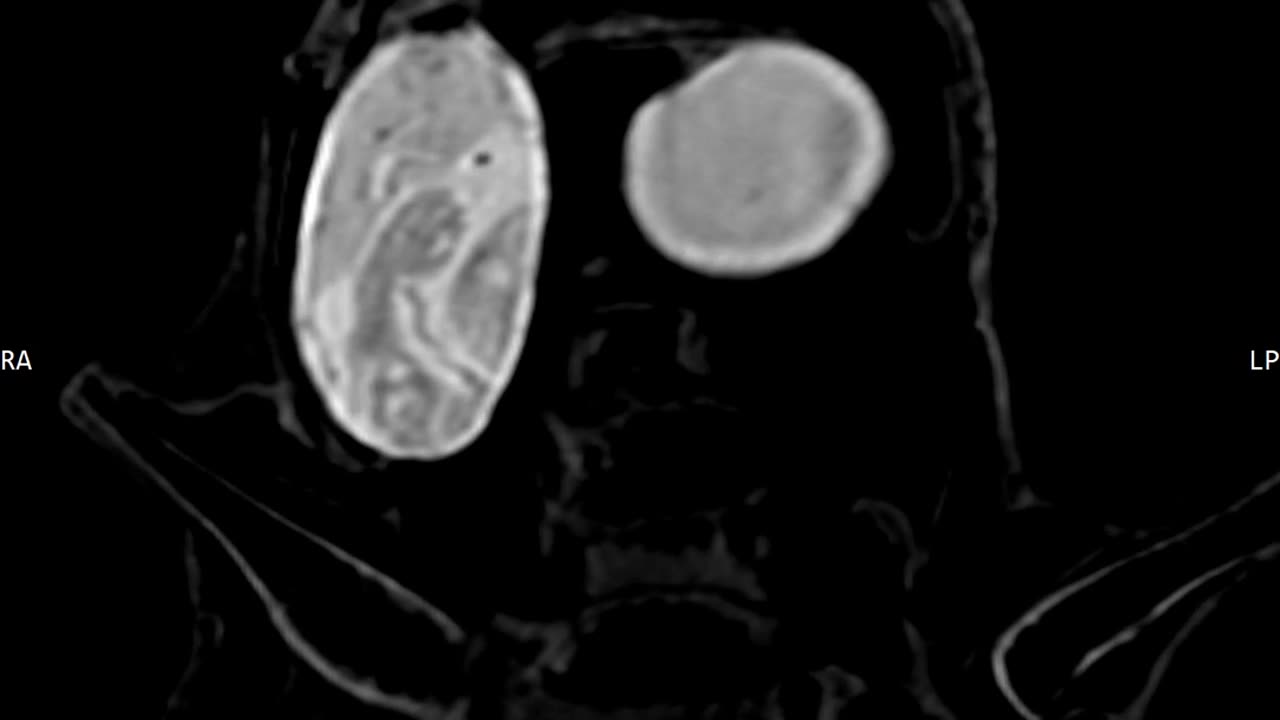

🕵️♂️🦆 Luisa's DICOM Files: Petrified Eggs with Babies Inside? | TheTruthAbove

In this footage, we explore Luisa's DICOM files and see petrified eggs that may still have the babies inside. This raises questions about Luisa's origins and the circumstances of her death. Could she be an ancient alien or a previously unknown species? 🦆 👉 For more compelling evidence and to uncover the truth, make sure you Like & Subscribe! #UFO #Aliens #DICOM #Mystery #TheTruthIsOutThere